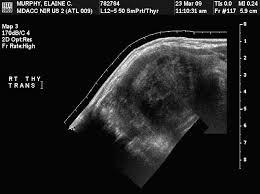

Ultrasonography Of The Thyroid Endotext Ncbi Bookshelf from www.ncbi.nlm.nih.gov A thyroid nodule can feel like a bump on the side or in the middle of the throat. Ultrasound is used to see the thyroid gland and the lymph node of the neck. Throat cancer is a condition that is characterized by the development of malignant tumors in the throat (pharynx), voice box (larynx) or tonsils. The cells are then looked at closely in the lab. In fact, the risk of cancer in any individual with thyroid nodules is. Some different types of cancers that can be detected. Throat cancer refers cancer that develops in your throat (pharynx) or voice box (larynx). Two in three cases of thyroid cancer occur in people under age 55, and 75%.

Ultrasound is often one of the first line tests in the detection of cancer. Keep in mind, however, that an ultrasound alone cannot make the diagnosis of cancer. Ultrasounds can produce false positives. Thyroid nodules are lumps that can appear in the thyroid gland in front of the throat. They increase with age and, in fact, if you look with sensitive measures like ultrasound, over 50% of people will have thyroid nodules by the age of 50 or 60. This test will usually help determine that the nodule has a low chance of being cancerous (has characteristics of a benign nodule), or that it has some characteristics of a cancerous nodule, and therefore a biopsy is indicated. Ultrasounds are not useful for treatment monitoring. While it can't diagnose cancer, it can detect the abnormal tissues that may possibly be cancerous. A small transducer (probe) both transmits sound waves into the body and records the waves that echo back. My 3.8 year old's neck ultrasound shows chain of lymph nodes bilaterally with largest on right 14mm by 6mm and largest on left 13mm by 6mm,the left one is there since a year.few intraparotid largest 5mm.thyroid & both submandibular normal. Staging head and neck cancers The most common symptom of thyroid cancer is a hard lump on the neck—but most patients experience no symptoms at all. Doctors often use them to guide a needle during a biopsy.

Ultrasound imaging can help determine the composition of lump, distinguishing between a cyst and a tumour. The survival rate in this type of cancer can be as high as 90 percent provided it is detected early in stage i itself. Throat cancer can develop in any part of the throat. The ultrasound can help to show whether a cyst has any solid areas as it is more likely to be cancer. Two in three cases of thyroid cancer occur in people under age 55, and 75%.